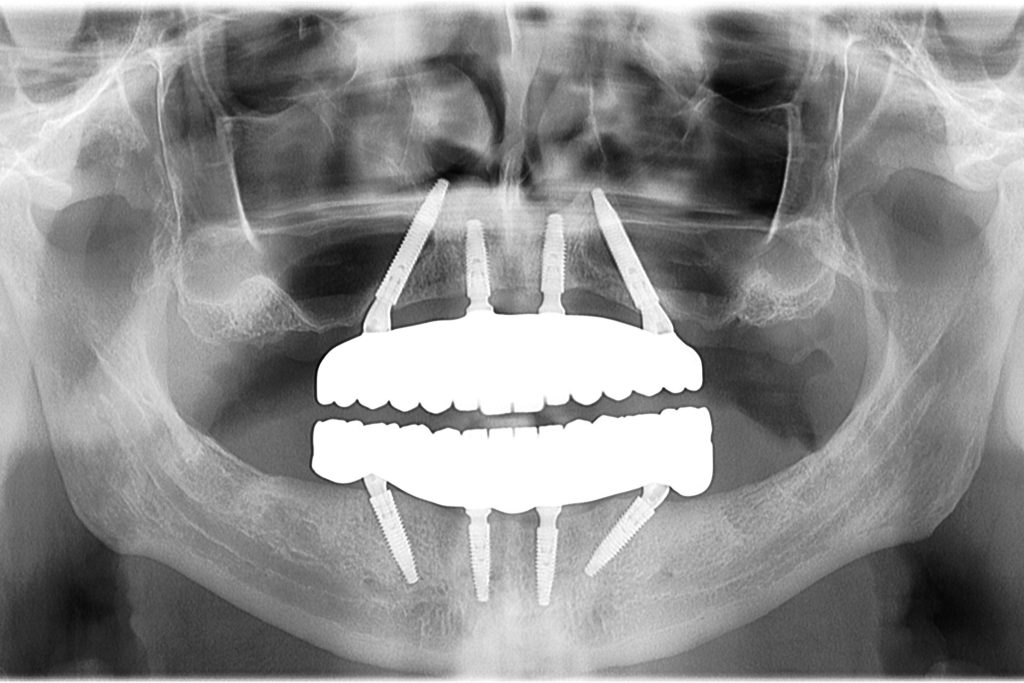

Двострука All-on-4 операција у Београду

Контролни панорамски рендгенски снимак одмах после операције који приказује Neodent GM Helix имплантате

Рентгенски снимак контроле показује оптимално нагибање имплантата за двоструку All-on-4 стабилност и савршено прилагођавање цирконије.

Коначни рентгенски снимак потврђује савршено прилагођавање рестаурација и здрав периоимплантни кост.